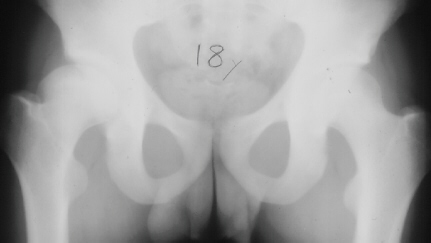

The parents first noted at the time the patient was 10y and 9 m old that he would limp on the right side after a full day of activity. He also started to have a occasional hip pain. Since the hip pain became progressively worse, he visited local clinics and was referred to AIDI at the age of 11y and 3 m. At the first examination abduction was 40 degrees bilaterally but internal rotation was limited to 0 degree on the right. The leg lengths were equal and no Trendelenburg sign was observed. X-ray showed the decreased epiphyseal height and medial joint opening. Snyder sling was started. At 12 years of age, internal rotation was still limited 20 degrees compared to 35 degrees on the left side but the left hip pain was asymptomatic. At 13 years of age, X-ray showed the regenerated head, so the Snyder sling was stopped and weight bearing was started. The Snyder sling had been applied for 2 years. At 16 years of age, ten degrees limitation of internal rotation as compared to the opposite side was still observed but the patient was asymptomatic.

11 yrs 3 mos, , 12 yrs, 13 yrs 8 mos , 17 yrs , 18 yrs.